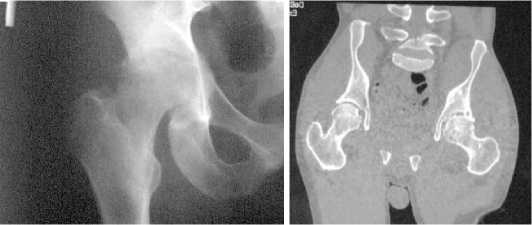

У 7 пациентов на фоне протекания септического коксита были отмечено формирование значительных анатомических изменений тазовой кости в области вертлужной впадины, в частности, – недостаточность верхнего края вертлужной впадины, что не позволяло устойчиво имплантировать головку цементного спейсера. В таких случаях на 1-м этапе хирургического лечения была осуществлена установка спейсера с созданием цементного надацетабулярного навеса по запантентованной методике (рисунок 3) [33].

Рисунок 3 . Спейсер с армированным навесом у пациента с кокситом и дефектом тела подвздошной кости